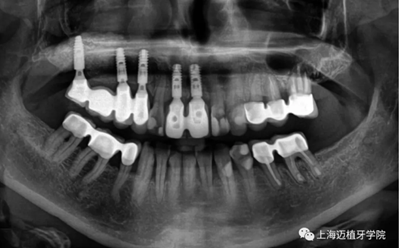

術(shù)前照,生物骨材料植骨失敗,植體暴露,生物骨材料沒有成骨(如圖),垂直向和水平向都受到感染

植體取出后,可以清晰地看到骨粉未成骨,還是顆粒狀